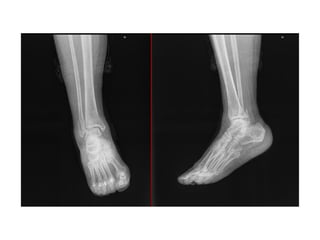

NOMBRE:TOLENTINO CRUCES JORGE ALEXANDER

NSS:3008870166 3M2014OR

URGENCIAS A

Edad: 10 AÑOS

Comorbilidades: NINGUNA

Fecha de la lesión: 13/09/25

Mecanismo de lesión: CAIDA DE TRAMPOLIN

Laboratorios: DENTRO DE NORMALIDAD

Valoraciones: NA

Diagnósticos: FRACTURA DE LA BASE DEL 5TO MTT DE PIE DERECHO (JONES)

Cirugía Proyectada: REDUCCION CERRADA VS ABIERTA FIJACION PERCUTANEA A BASE DE 5TO MTT DE PIE DERECHO

Material OSS Solicitado: NA

NOMBRE:TOLENTINO CRUCES JORGEALEXANDER NSS:3008870166 3M2014OR URGENCIAS A Edad: 10 AÑOS Comorbilidades: NINGUNA Fecha de la lesión: 13/09/25 Mecanismo de lesión: CAIDA DE TRAMPOLIN Laboratorios: DENTRO DE NORMALIDAD Valoraciones: NA Diagnósticos: FRACTURA DE LA BASE DEL 5TO MTT DE PIE DERECHO (JONES) Cirugía Proyectada: REDUCCION CERRADA VS ABIERTA FIJACION PERCUTANEA A BASE DE 5TO MTT DE PIE DERECHO Material OSS Solicitado: NA